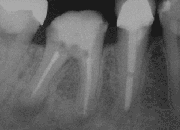

- bei einer resorbierenden apikalen Parodontitis (röntgenologisch sieht man eine Aufhellung an der Wurzelspitze);

Nach Durchführung einer Lokalanästhesie erfolgt die Mobilisierung eines Mukoperiostlappens (Zahnfleischlappen). Anschließend wird mit einer Kugelfräse unter Kühlung mit physiologischer Kochsalzlösung der Knochen über der Wurzelspitzenregion entfernt (Osteotomie) und der pathologische Befund entsprechend seiner Ausdehnung dargestellt. Das granulomatös entzündliche oder zystische periapikale Gewebe wird entfernt und die Wurzelspitze abgetrennt und geglättet. Am Resektionsquerschnitt wird die Wurzelkanalfüllung auf Dichtigkeit überprüft, gegebenenfalls muss die Wurzelkanalfüllung erneuert oder eine retrograde Wurzelfüllung gelegt werden. Dabei werden die Wurzelkanäle von der Gegenseite, d. h. an der Wurzelspitze, im Rahmen einer Wurzelspitzenresektion verschlossen.